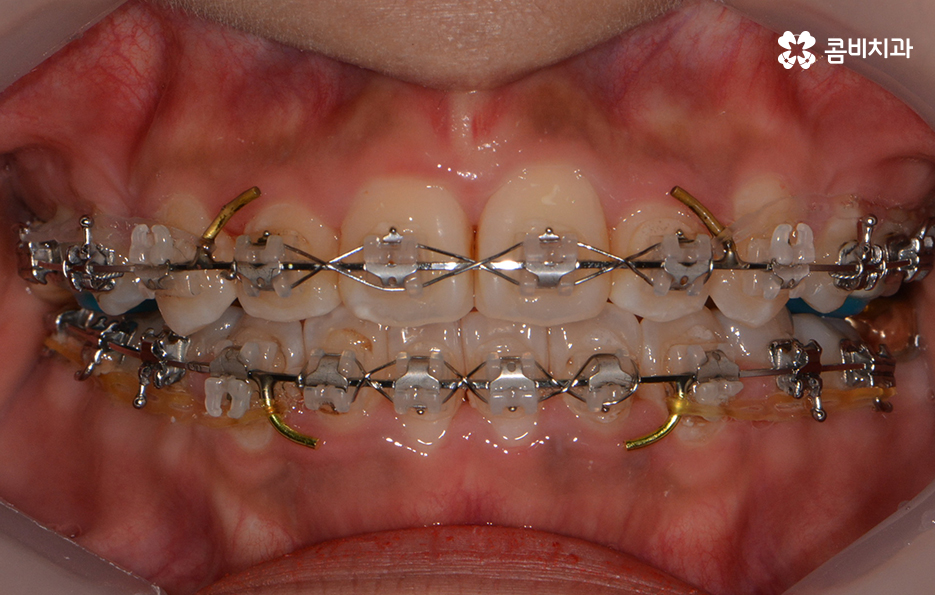

교정이 시작된 후 경과 - 발치를 했던 부위의 치아 사이 빈 공간이 사라짐